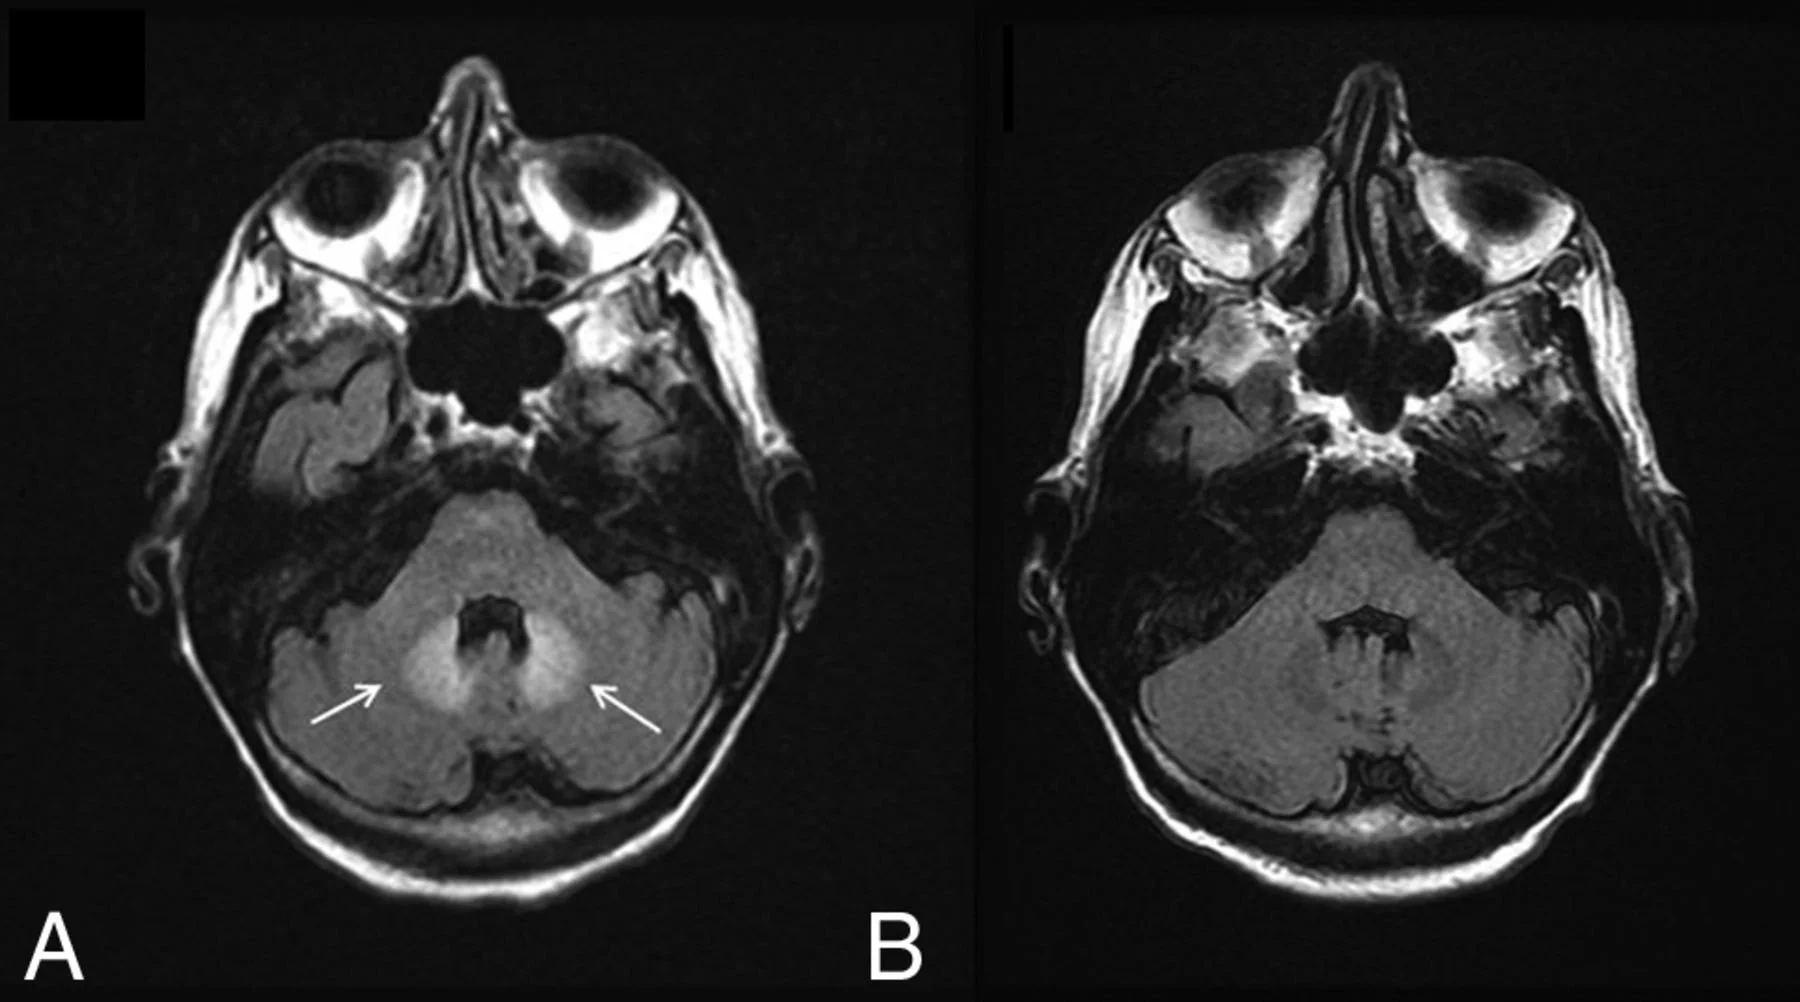

Barbell sign

Image showing abnormally hyperintense dentate nuclei.

Note: This image is not PML it just shows anatomy of dentate nuclei well since they are so abnormally bright here,